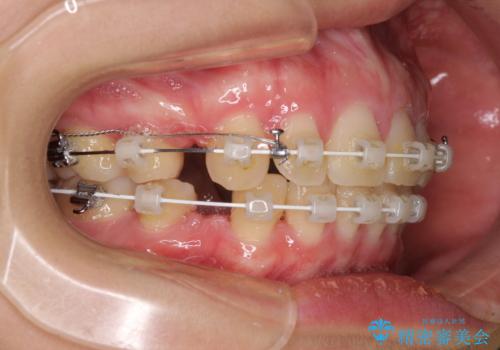

- 矯正装置

- 審美装置

- 治療期間

- 3年1ヶ月

左右ともに下顎に対して上顎歯列が前方位にある上顎前突であったので、上顎歯列全体を後方に移動させることで上下咬み合わせを改善し、その上で抜歯矯正により口元の突出感を改善させていきました。